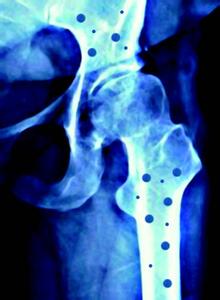

骨质疏松症是以骨量降低、骨组织的化学成分正常、显微结构退行性变和骨折的危险性增高为特征,它的临床表现为软弱无力、腰背痛、骨疼、骨骼变形。在早期可无明显的自觉症状,它通常是慢慢地、悄悄地潜入体内而不为察觉,只有当骨质丧失达30%时,才可能出现驼背和全身变矮情况,很多患者常因此而发生骨质疏松性骨折。如在美国骨质疏松症患者约有二千万,45岁以上老年人每年由于本症所致的自发性骨折近130万,而在过去的30年中,骨质疏松症导致髋骨骨折的发病率在香港老年人中上升了2倍,在70岁以上的香港人之中,每年有百分之一会折断髋骨。骨质疏松主要分为两大类:即原发性骨质疏松和继发性骨质疏松。继发性骨质疏松往往是由于某些疾病或某些原因诱发,原发性骨质疏松是由于年龄增加或妇女绝经后骨组织发生的一种生理性变化,还有一种原因不明的特发性骨质疏松症,不是出现在老年,而是发生在青壮年或少年,此病例多有遗传家族中。但不论是先天还是后天,是原发还是继发,都与钙缺乏关系密切。患者首先是损失骨母质,逐渐脱钙。我国近年来对骨质疏松症的研究发现,骨骼中钙的损失可在40岁或更早出现。